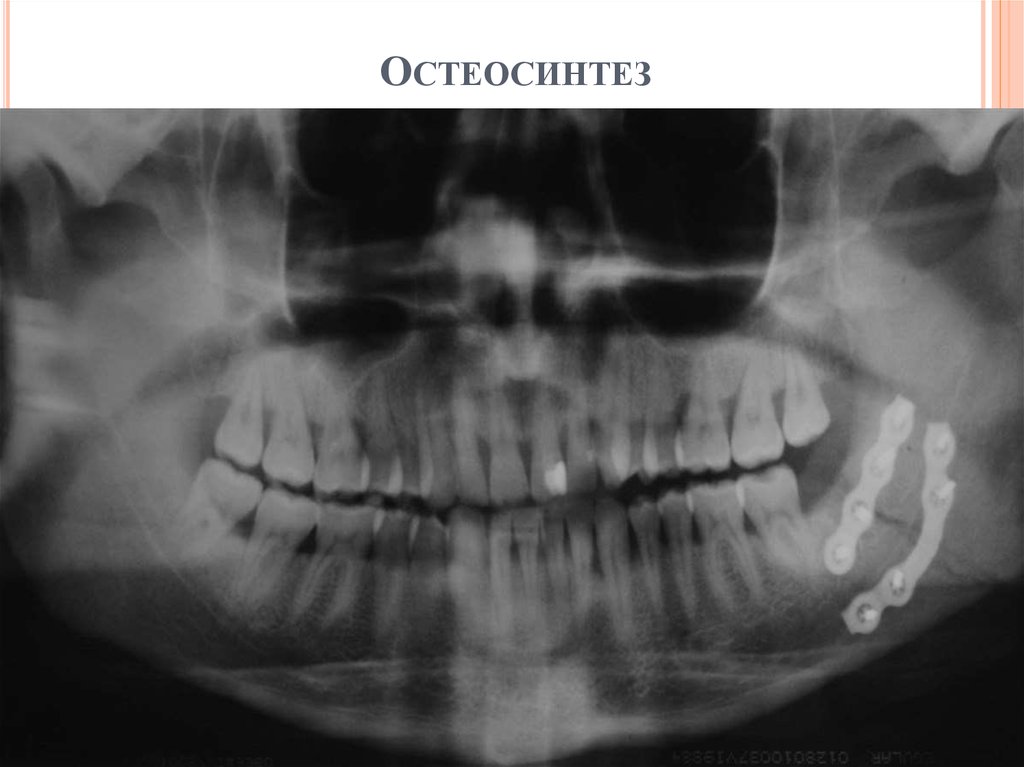

5. Остеосинтез

ОСТЕОСИНТЕЗ